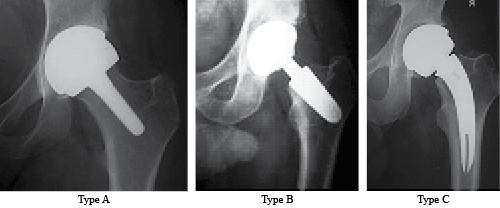

Figure 2: Classification of short stems according to the regions they occupy or invade. Type A) It occupies the head-collar-metaphysis regions. (E.g., Birmingham Mid-Head Resection) Type B) It occupies the collar-metaphysis regions. (E.g., Silent short stem).Type C) It occupies the collar-metaphysis-diaphysis regions. (E.g., TSI(tm) Neck Sparing Stem).